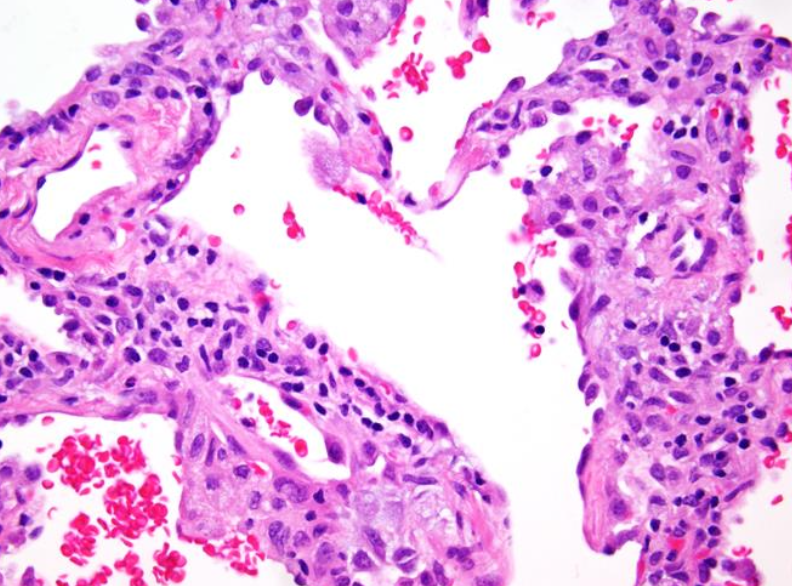

Asma

Solo ver